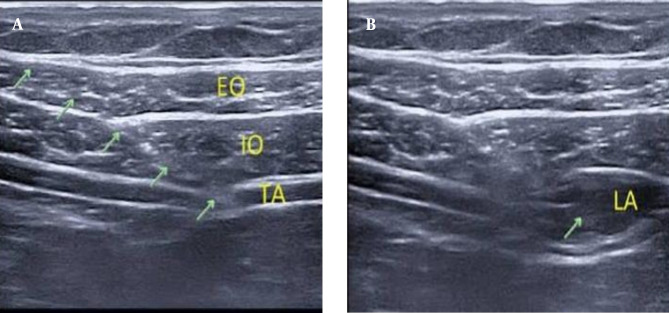

Methods: This randomized, controlled, single-blinded clinical study was conducted on 50 individuals aged 20 to 60 years, of both genders, with American Society of Anesthesiology (ASA) grade I and II physical status, undergoing LC. Subjects were allocated using a computer-generated randomization table into two equal groups: Group A received an ultrasound (US)-guided ESP block, and group B received a US-guided OSTAP block.

Abstract Image